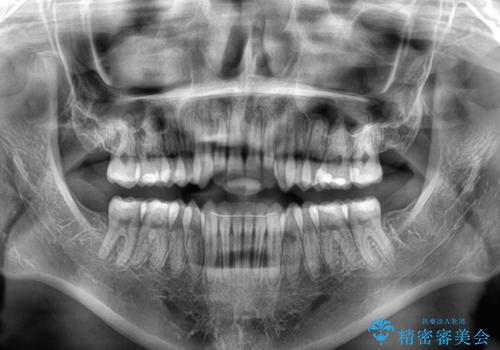

- 前歯の開咬を気にして来院された患者様です。

開咬の治療は、前歯を閉じるように動かすとともに、上下臼歯を圧下(骨内にめり込ませる)させることで進めて行きます。

インビザラインは臼歯の圧下を効果的に行えるため、インビザラインを用いて矯正治療を行うこととしました。